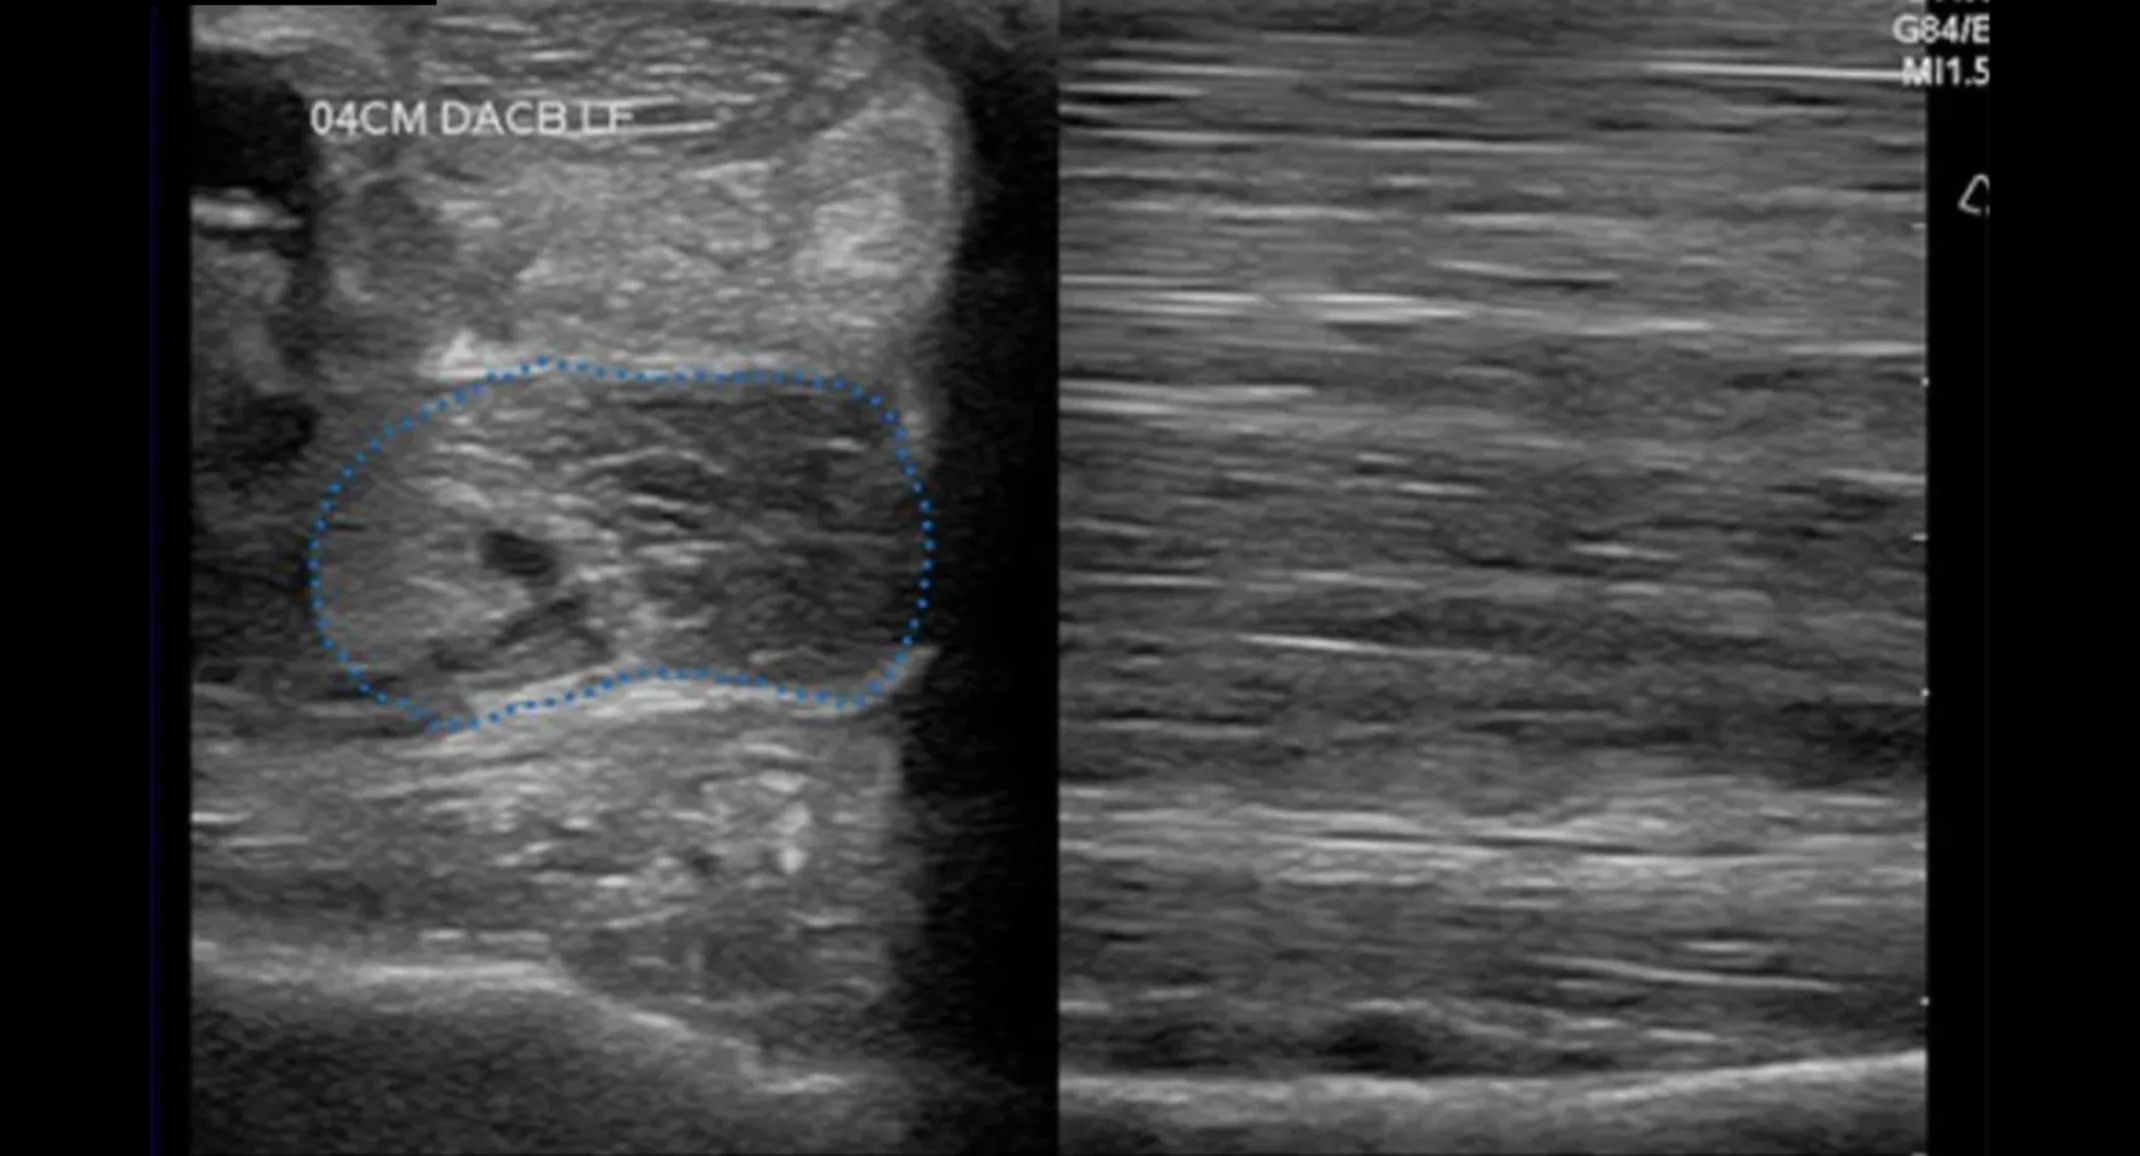

Ultrasound examination confirmed desmitis of the ICL. The ligament showed an increase in the cross-sectional area and had diffuse hypoechogenicity.